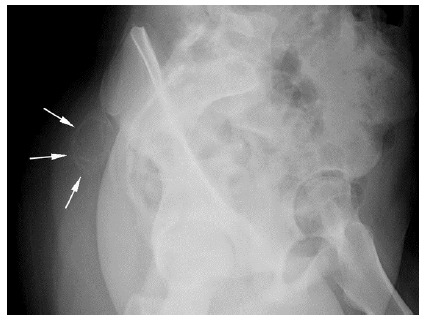

Findings: Palpation of the right buttock indicated a tender mass. Investigation by musculoskeletal ultrasound detected a large hypoechoic lesion. An MRI revealed patterns of calcification that were inconclusive in differentiating between a malignant or benign lesion. Macroscopic and microscopic histological examination, as well as immunohistochemistry, were consistent with myositis ossificans (MO), a non-malignant condition. The patient improved remarkably within three months of treatment with rest, non-steroidal anti-inflammatory drugs (NSAIDs) and extracorporeal shock wave therapy (ESWT).